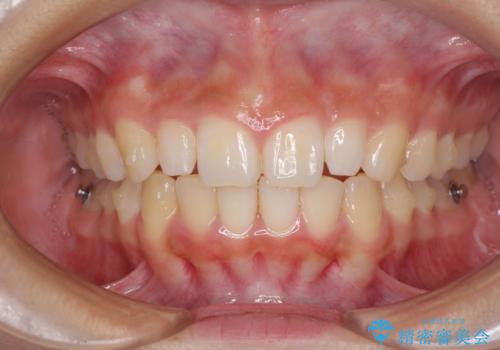

前歯のデコボコを治したい インビザラインによる矯正治療

- 前歯のデコボコ気になるとのことで来院された患者様です。

上下顎ともに歯列全体の後方移動とIPR(歯と歯の間を削る)によってデコボコが解消するように設計し、インビザラインにより治療を行うこととしました。

上顎左右前歯に矮小歯があるため、上顎の奥歯は下顎に対して相対的に前方に位置することになりました。

それでも奥歯の咬みにくさはなく、患者様には大変満足していただきました。